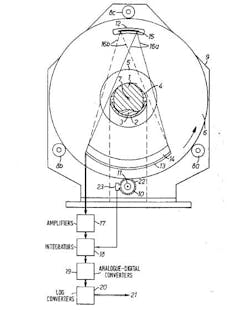

First, he would conceptually divide the brain into consecutive slices – like a loaf of bread. Then he planned to beam a series of X-rays through each layer, repeating this for each degree of a half-circle. The strength of each beam would be captured on the opposite side of the brain – with stronger beams indicating they’d traveled through less dense material.

But there was a problem: EMI wasn’t involved in the medical market and had no desire to jump in. The company allowed Hounsfield to work on his product, but with scant funding. He was forced to scrounge through the scrap bin of the research facilities and cobbled together a primitive scanning machine - small enough to rest atop a dining table.

He knew there were no grants they could obtain quickly, but reasoned the U.K. Department of Health and Social Security could purchase equipment for hospitals. Miraculously, Ingham sold them four scanners before they were even built. So, Hounsfield organized a team, and they raced to build a safe and effective human scanner.

Meanwhile, Hounsfield needed patients to try out his machine on. He found a somewhat reluctant neurologist who agreed to help. The team installed a full-sized scanner at the Atkinson Morley Hospital in London, and on Oct. 1, 1971, they scanned their first patient: a middle-aged woman who showed signs of a brain tumor.